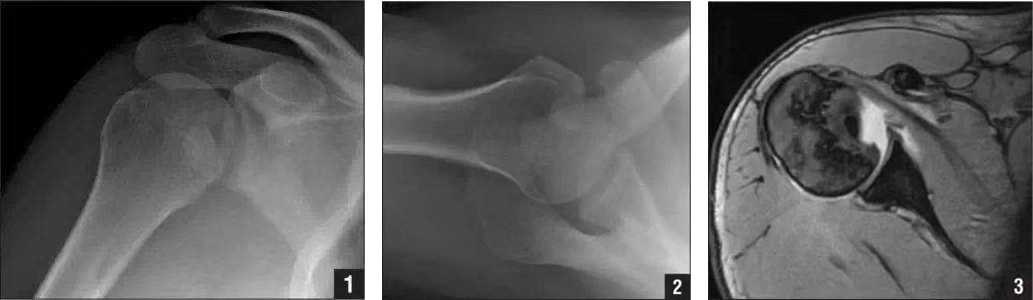

(2) Hill-Sachs、反 Hill-Sachs 损伤

肩关节脱位时,肱骨头和关节盂发生撞击,肱骨头表面凹陷性骨折。

肩关节前脱位时发生的肱骨头后外侧凹陷性骨折,是经典的 Hill-Sachs 损伤(Hill-Sachs lesion);而肩关节后脱位时发生的肱骨头前内侧凹陷性骨折,是反 Hill-Sachs 损伤(Reverse Hill-Sachs lesion/ McLaughlin lesion)。

A.Hill-Sachs 损伤的 X 片;B.Hill-Sachs 损伤的 MR 片;C.Hill-Sachs 损伤的 CT 片。

1. 正位片示肱骨头损伤;2. 侧位片示反 Hill-Sachs 损伤;3.MRI 示反 Hill-Sachs 损伤程度。